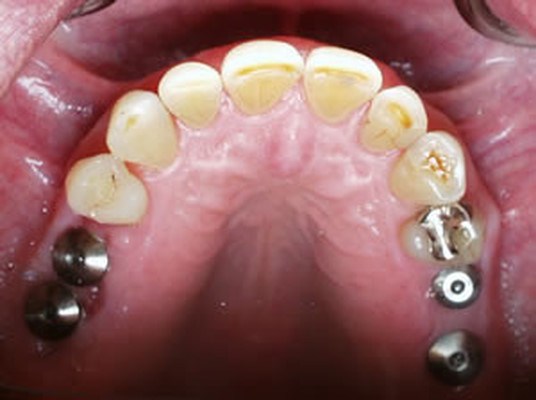

치아 중 어금니는 음식물을 섭취할 때 잘게 부수어 소화가 잘 되도록 돕는 치아입니다. 그러나 음식물을 섭취할 때 음식물 찌꺼기가 남거나 칫솔이 잘 닿지 않는 부위로 충치 발생이 잦은 부위이기도 한데요. 어금니는 충치가 생기기 쉬운 치아로 손실 및 상실로 인한 임플란트 관리를 많이 하는 부위이기도 합니다.

치주질병이나 잇몸 염이 자주 발생할 수 있어 잇몸 관리와 병행하는 사례도 많은 편이죠. 이처럼 어금니가 소실되면 정상적인 저작 기능이 힘들어 식사하는데 매우 큰 불편함을 느낄 수 있습니다. 이 경우 임플란트를 통해 자연 치아에 가까운 씹는 힘과 형태를 되찾을 수 있으며 저작 능력이 강조되는 어금니를 대체하는데 있어 어금니임플란트는 가장 효율적인 관리라고 볼 수 있습니다.